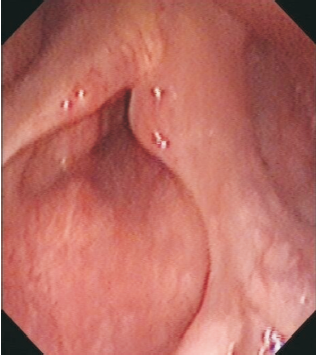

查体:PS=1分, 左侧声带全长及前联合处可见菜花样新生物、质韧, 双侧声带活动度可, 闭合不严, 发音嘶哑。全身浅表淋巴结未触及肿大。

颈部增强CT(2010-12-28):左侧声带小结节, 符合声门癌, 考虑累及前联合、右侧室带, 见图1。

入院诊断:左侧声门型鳞状细胞癌cT1bN0M0Ⅰ 期。